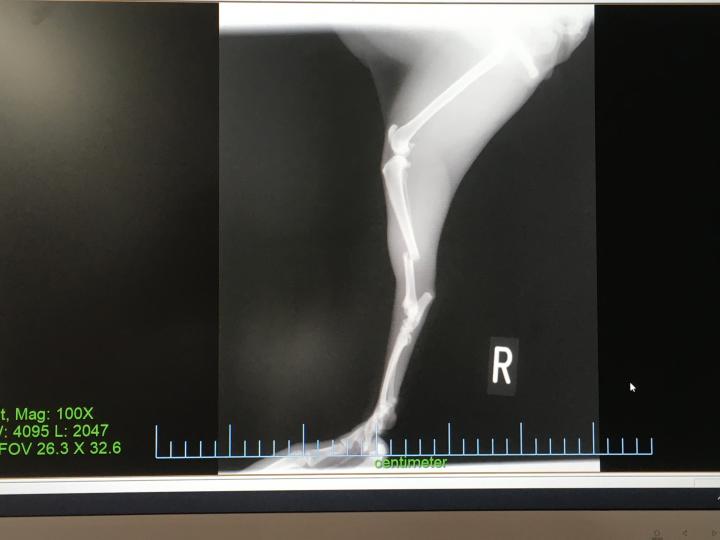

てことで骨折

ビフォー